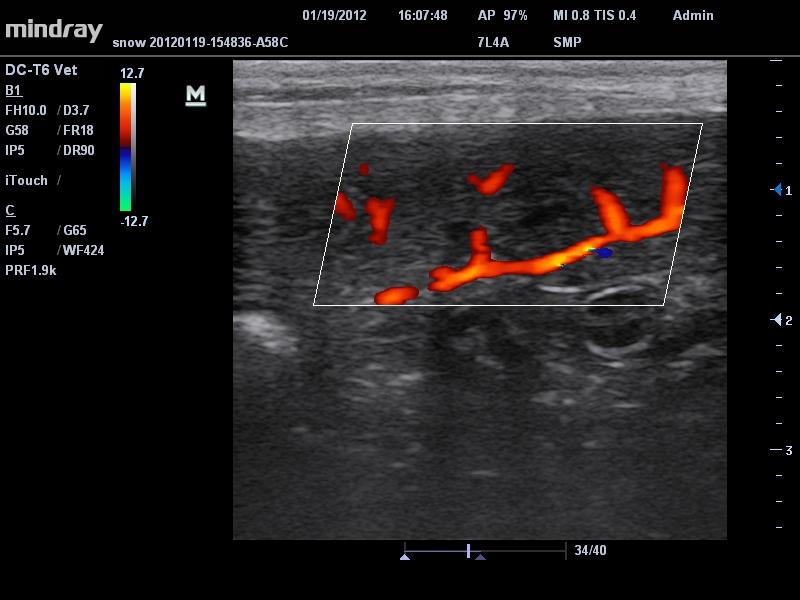

• Линейный ультразвуковой датчик Mindray 7L4A

Да

Цветовой допплер:

• Режимы сканирования: B/M/CFM/PDI/Направленный PDI/PW, HPRF, Тканевая гармоника, М- и цветной М-режим.